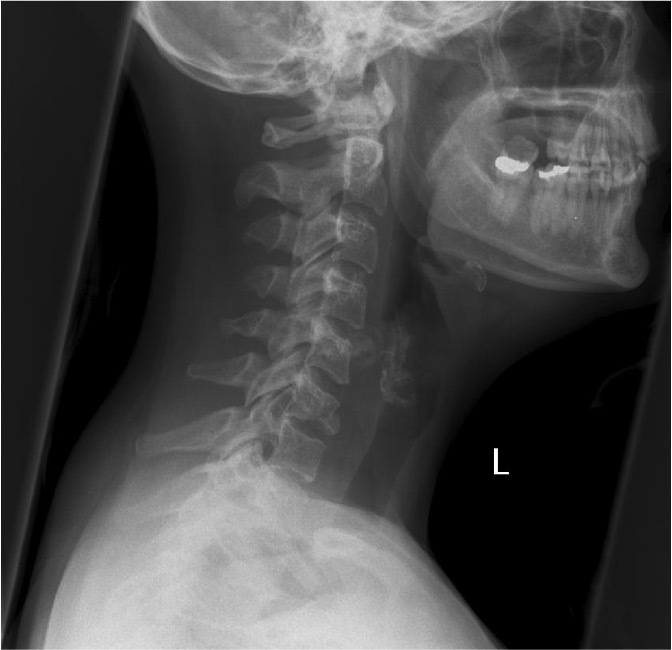

C6 fracture

Pneumoperitoneum